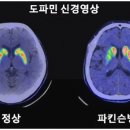

바이오메딕스는 줄기세포로부터 도파민 신경세포를 고수율로 분화시키는 기술을 개발하여 캐나다에서 특허를 획득하였습니다. 이는 파킨슨병의 근본적인 치료...의 타바파돈(Tavapadon): 애브비는 파킨슨병 치료제인 타바파돈의 후기 임상시험에서 긍정적인 결과를 얻었습니다. 이는 초기 파킨슨병 환자들에게서 운동...